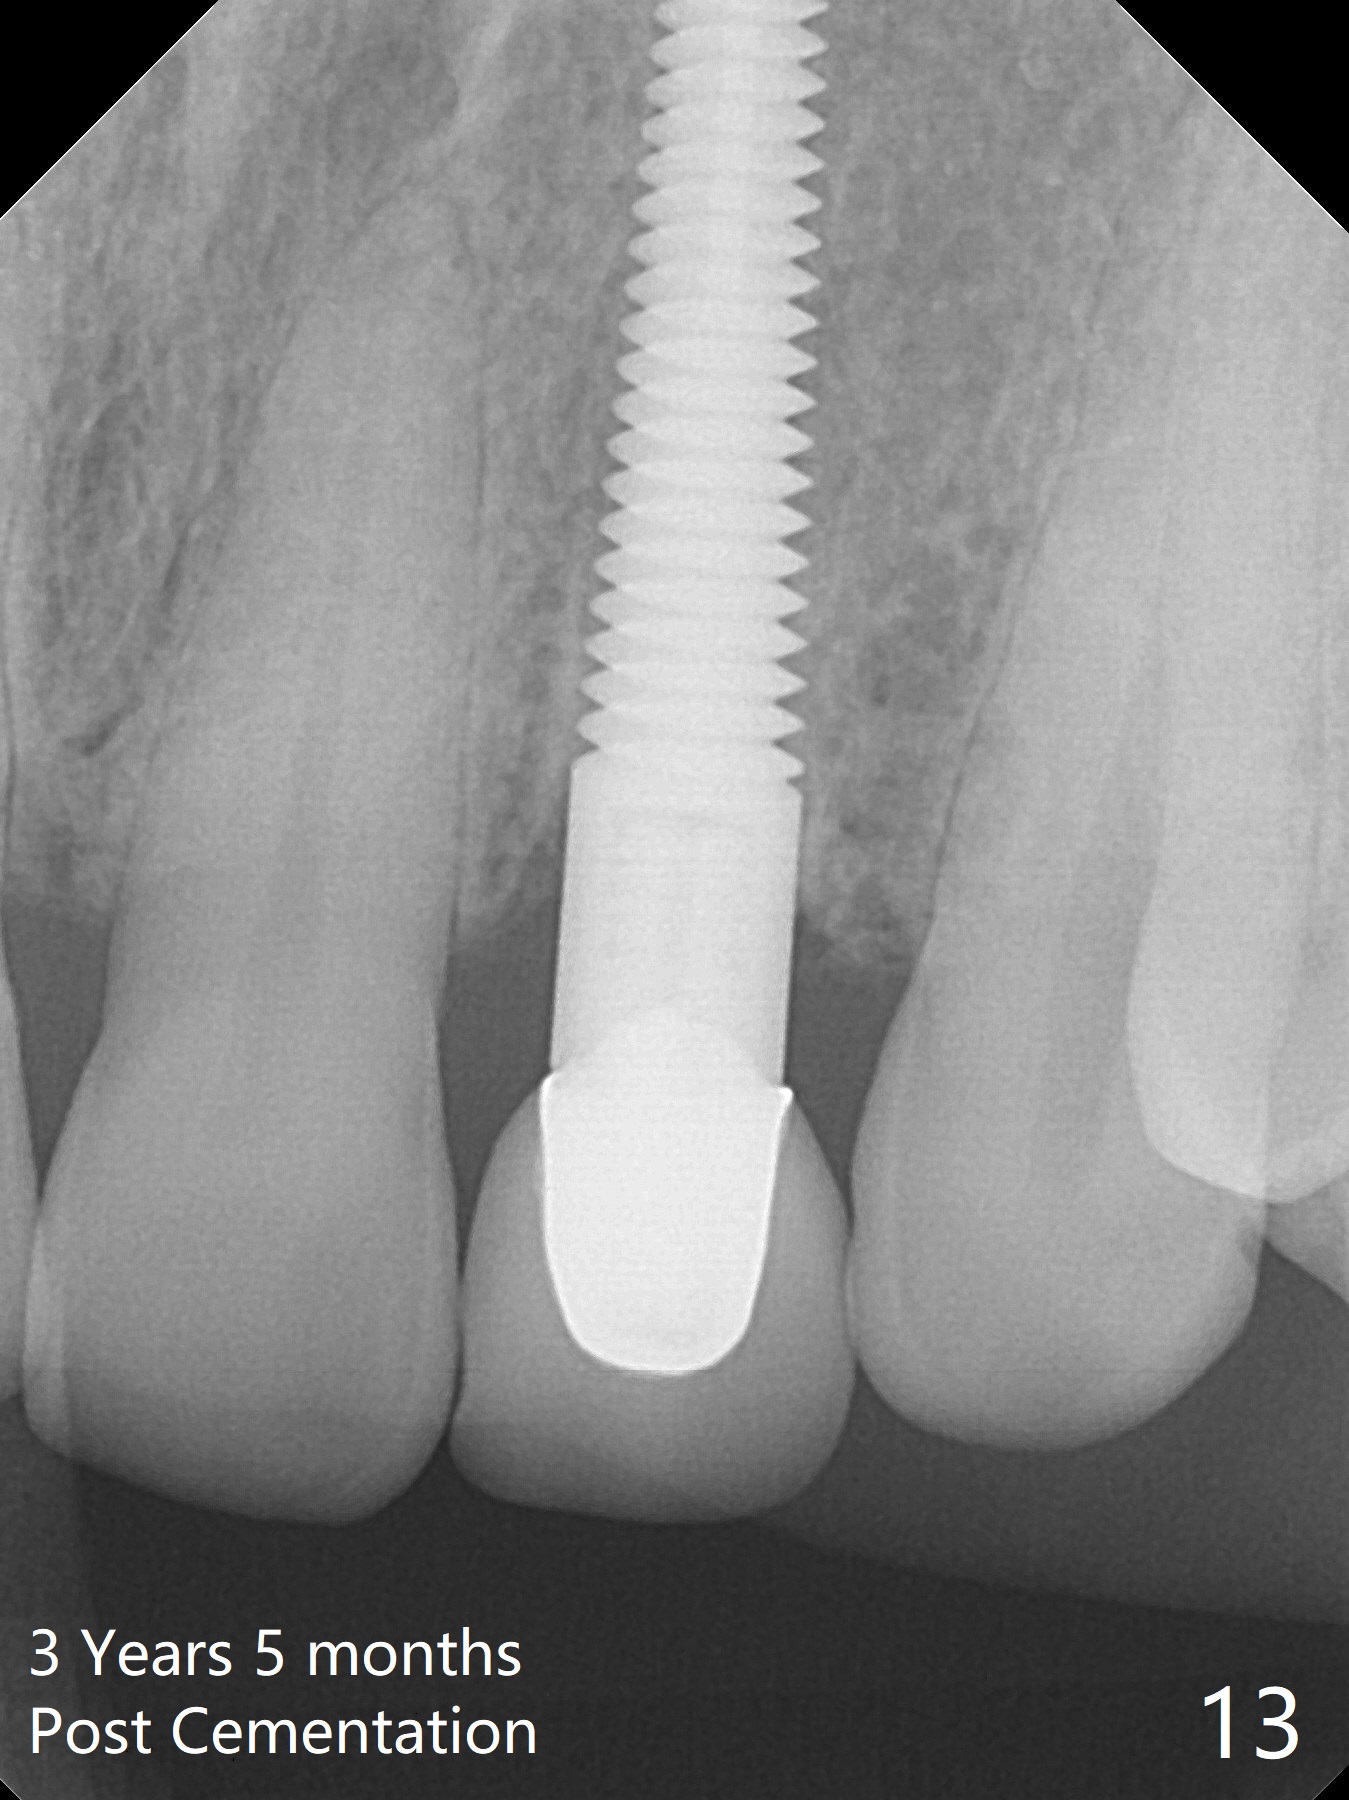

Dense bone forms immediately next to the implant 3 years 5 months post cementation (Fig.13) without gingival recession (Fig.14,15). In fact, the buccal plate maintains root contour over the implant (Fig.15 *). The root prominence remains 6 years 3 months post cementation (Fig.16-18 *). Appreciate the labial concavity associated with implant placement 6 years 9 months post cementation (Fig.19). The implant must have been placed quite palatal.